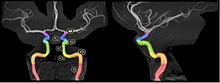

The segments of the internal carotid artery are as follows:

Segments of the internal carotid artery, delineated on an MRA of the head.